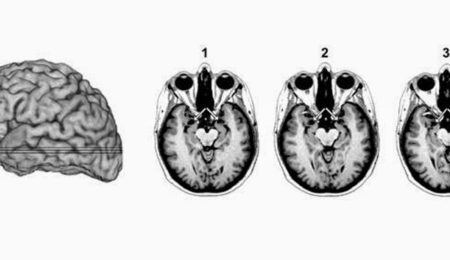

According To Science, You Will Be Fearless If You Remove This Part Of Your Brain

Researchers in the 1930’s conducted a research on animals and discovered that when they removed a certain part of a monkey’s brain, the animals turned fearless: they could approach snakes and bat them around with sticks without fear. They even played with the hissing tongues of the snakes. The experiment has been repeated numerous times in animals and the scientists have reached a consensus: when the amygdala is removed, animals lose any sense of fear.

The same experiment was conducted on humans and the results were similar, according to a study in the journal, Current Biology.

Justin Feinstein, lead author of the study and clinical neuropsychologist at the University of Iowa says that, “There’s not very many humans with this sort of brain damage, luckily for us, we had access to a patient, SM, and we studied her different fear behaviors and we read her personal diaries.”

Patient SM has holes where her amygdala should be due to lipoid proteinosis, a rare condition. According to the researchers, she reacted the same way the monkeys did; she has no fear of creatures like spiders and snakes that alarm most people ordinarily. She also tends to put her life at risk. On one occasion, she was attacked by a man with a knife while walking alone through a park, “the following day, she again walked through the same park,” Mr. Feinstein said.

He and his colleagues are trying to coach the patient into being more careful. They believe that if they understand how SM’s mind works, they may be able to develop therapies for people with excessive amounts of fear, for example war veterans. “We may be able to dampen the effects of the amygdala. We can do that through psychotherapy and possibly through medication.” he said.